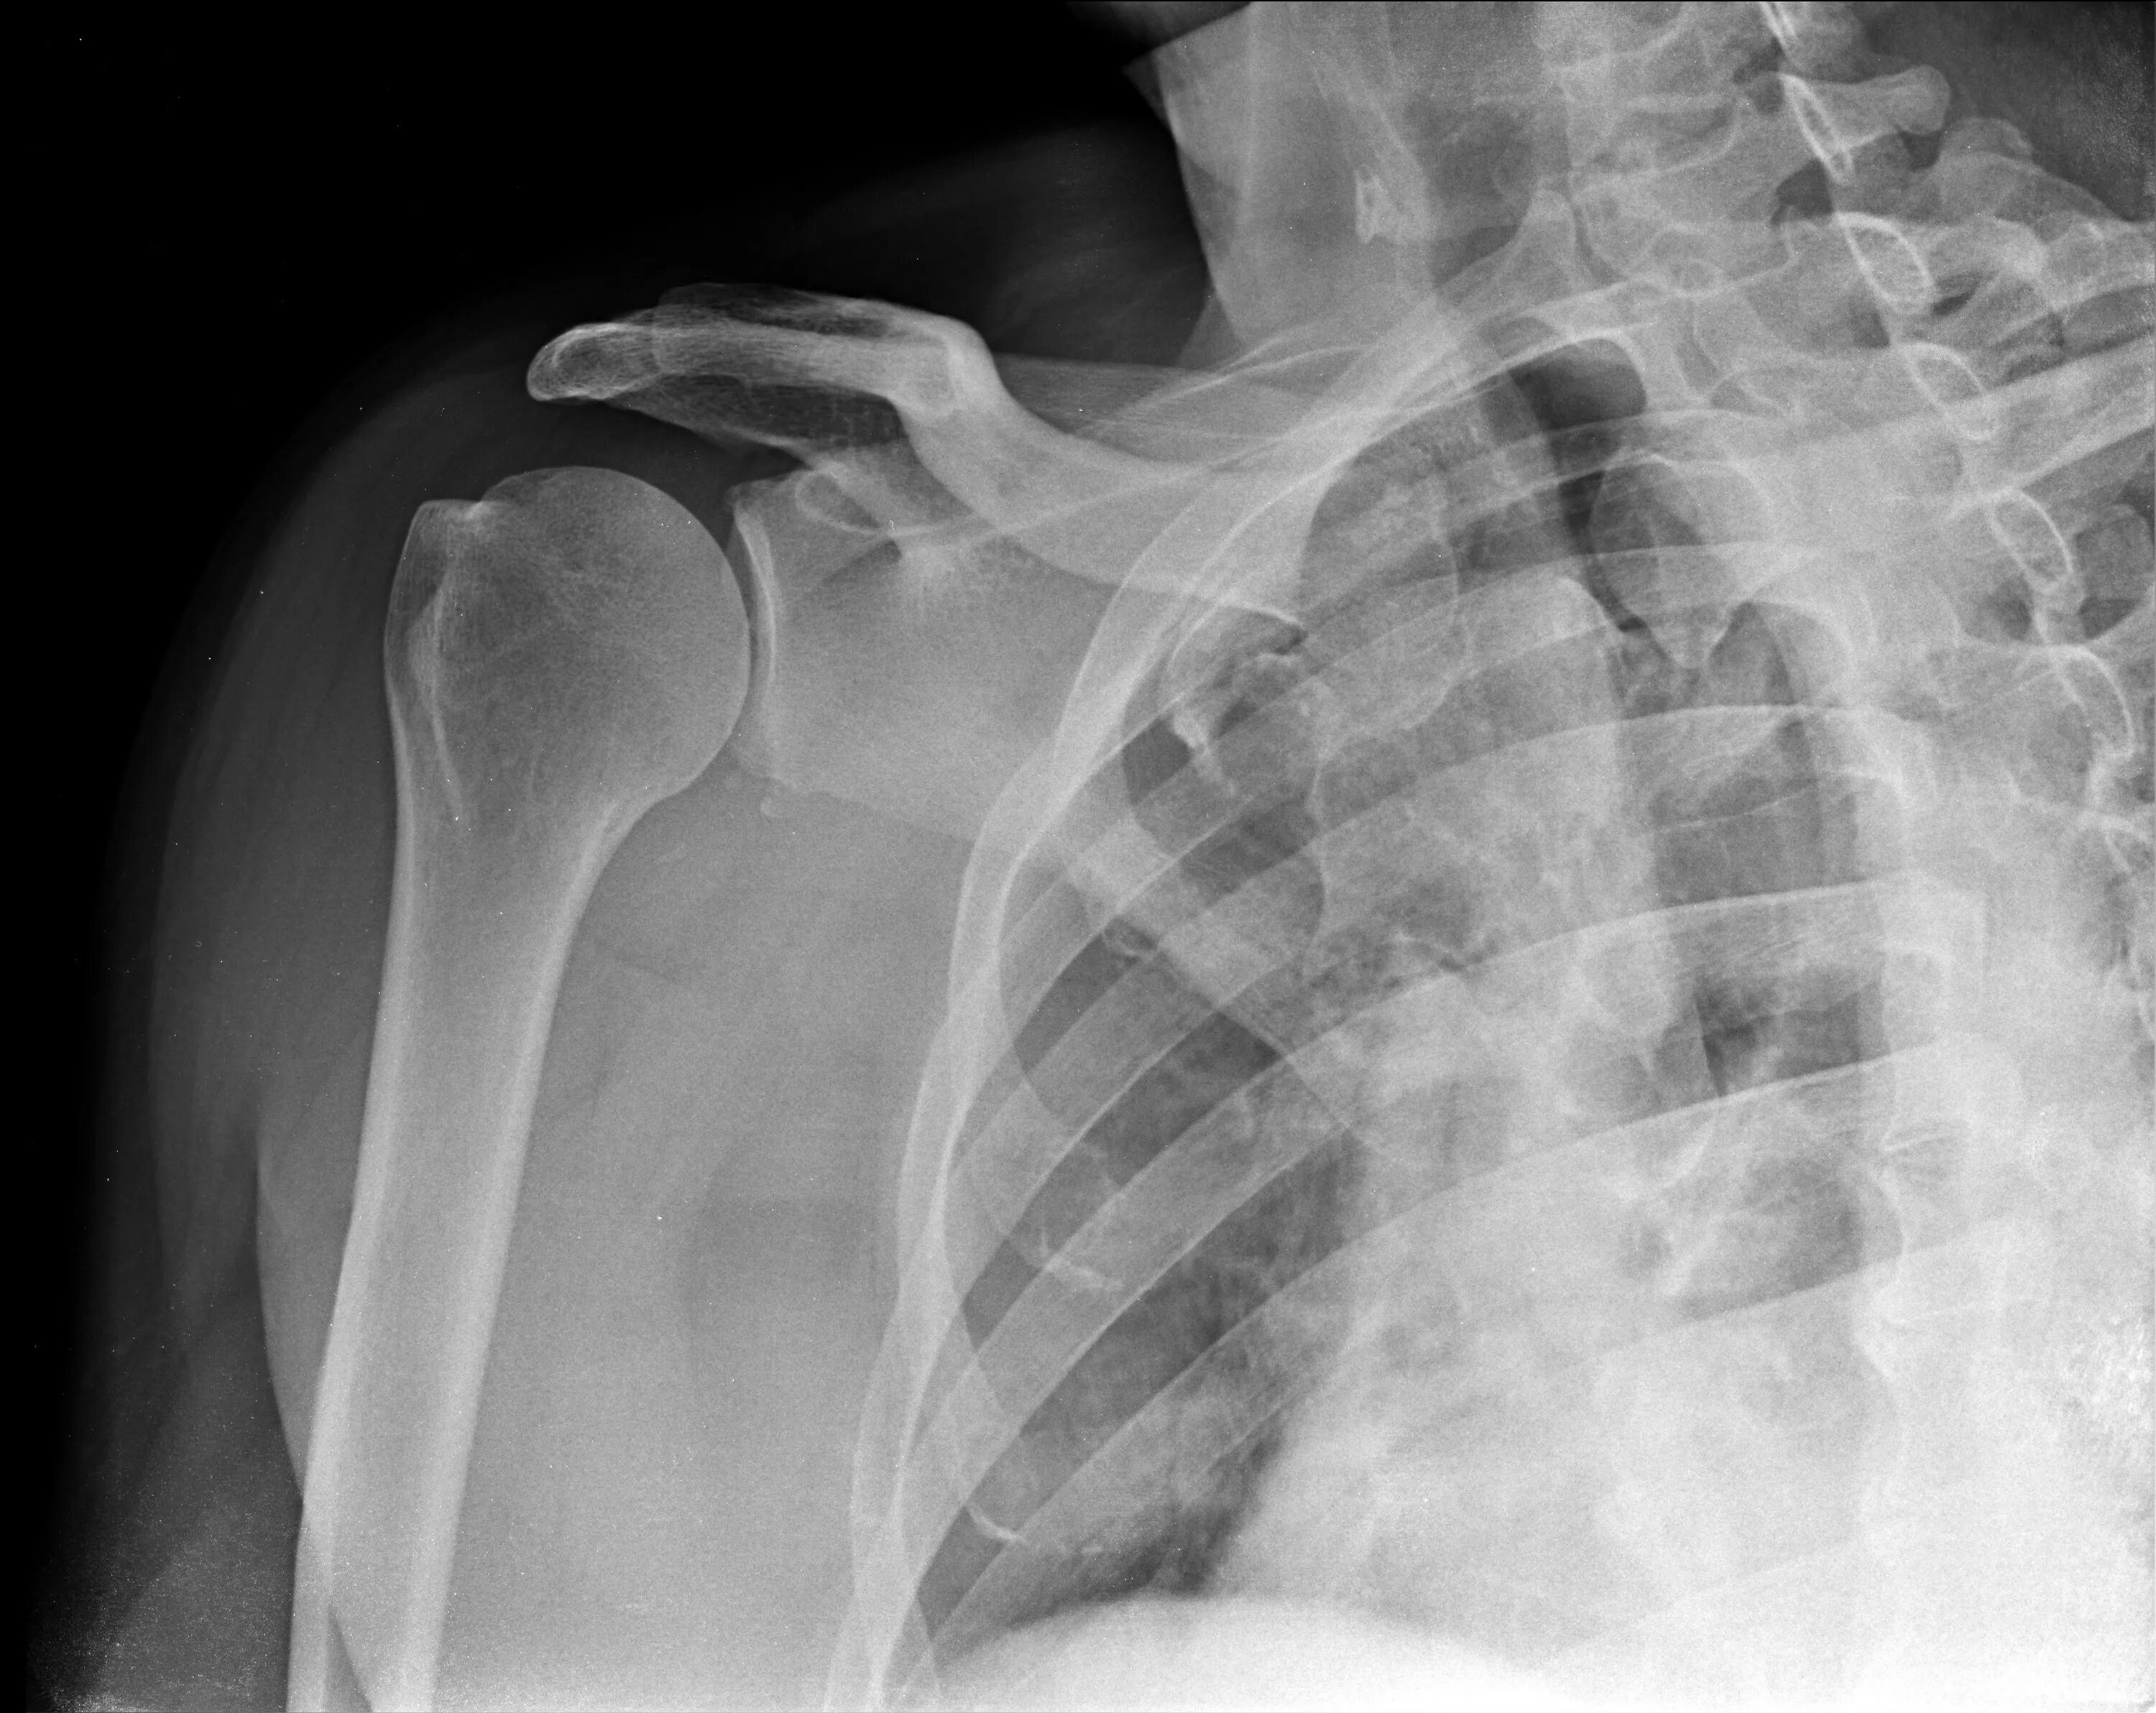

Перелом б бугорка